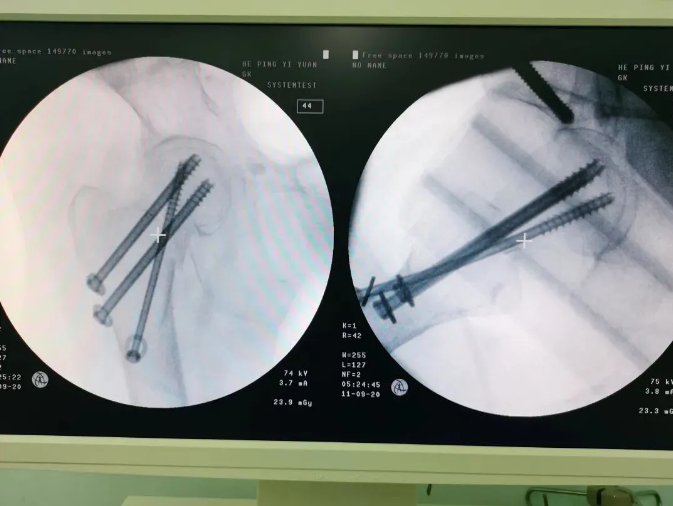

規(guī)劃入路

天璣機(jī)器人置入螺釘

螺釘置入后

天璣?骨科手術(shù)機(jī)器人的加入,能夠協(xié)助醫(yī)生為需要進(jìn)行手術(shù)的患者提供更安全、優(yōu)質(zhì)、高效的醫(yī)療服務(wù),幫助患者清除病灶,守護(hù)患者健康,提高患者生活質(zhì)量。在天璣?骨科手術(shù)機(jī)器人的協(xié)助下,術(shù)中患者切口僅三個小孔,出血量少;術(shù)后陳婆婆經(jīng)一段時間的康復(fù)訓(xùn)練便可下床活動,目前已康復(fù)出院。